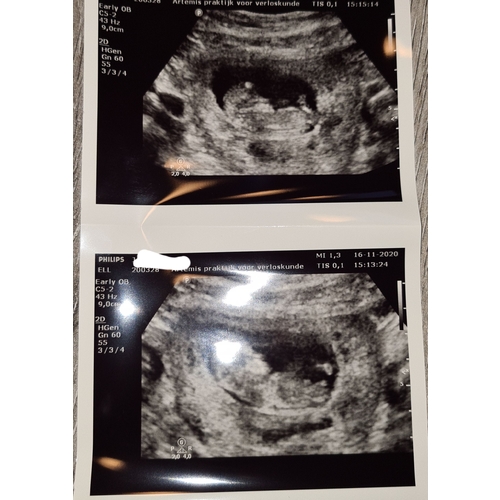

Vanmiddag de termijnen echo gehad, 19 oktober was ik 6 dagen terug gezet, vanmiddag bij de echo weer 6 dagen voorruit, de kleine deed het super, groeit goed en was een spring in het veld in de buik, heb een prachtig filmpje maar kan die niet plaatsen! Echt even een bevestiging van zwanger zijn! Ik heb 0.0 kwaaltjes dus maakte me toch wat zorgen dat het niet goed ging! Vandaag 11+4 wkn met de uitgerekende datum op 3 Juni 鉂も潳

Ahh, mooie echo!!! Ik had ook vandaag nu 11+1馃挄

Vandaag ook me 11 weken echo gehad馃挆馃挋 ...